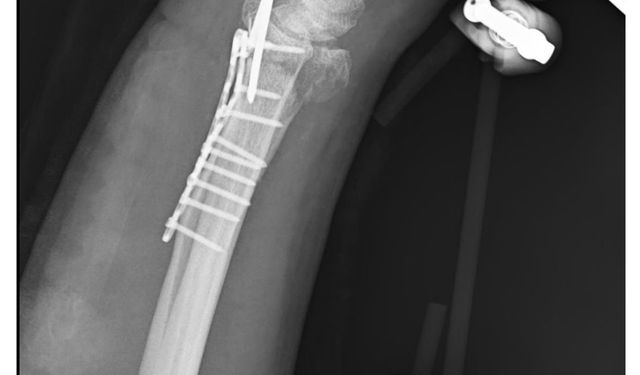

Akıma kapılan Furkan, doku nakliyle ayağa kalktı